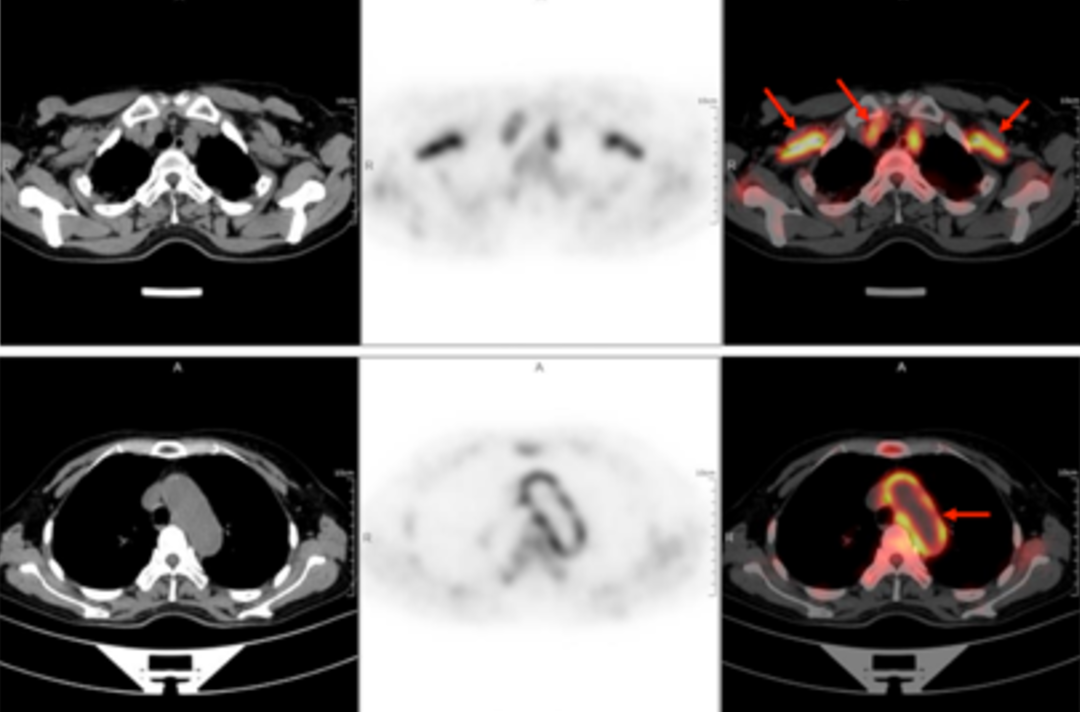

58歳の女性が40日以上前から断続的に発熱しているため受診しました。体温は38.9℃で、寒気、痰、喀血、胸痛、胸部圧迫感、息切れなどの症状はなく、倦怠感、肩関節痛が午後から夜間にかけて特に強く現れました。セファロスポリン系抗生物質の静脈内投与を2週間続けても改善は見られず、断続的な発熱が続いていました。外来診療では「原因不明の発熱」と指摘され、身体検査では明らかな診断上の特徴はありませんでした。血液検査の結果は以下の通りでした。赤血球沈降速度(最初の1時間):72mm、高感度C反応性蛋白:204. 20mg/lでした。その後、原因不明の発熱の原因を探るため、全身 F-FDG PET-CT 検査を行いました。

PET/CT 画像では,全身数カ所(両側内頚動脈,総頚動脈,腕頭動脈,両側鎖骨下動脈,腋窩動脈,胸部大動脈,腹部大動脈,両側総腸骨動脈,内腸骨動脈,外腸骨動脈,大腿動脈)に糖代謝亢進を伴う壁厚化を認め,炎症性変化によるものと判断しました。病歴、臨床症状、検査、画像所見を総合してT.A.と診断し、標準的な抗炎症治療を行ったところ、体温が低下し病状が改善しました。